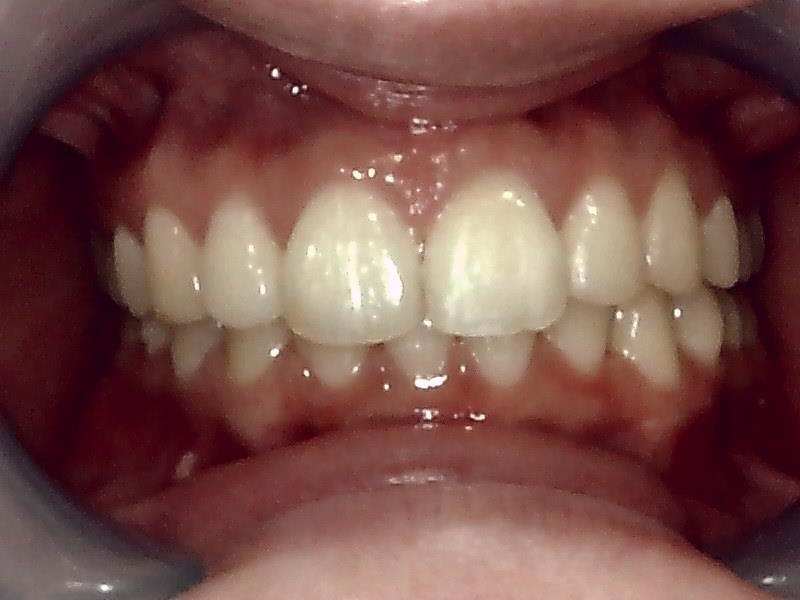

術前口腔内写真 正面観

術後の口腔内写真 正面観